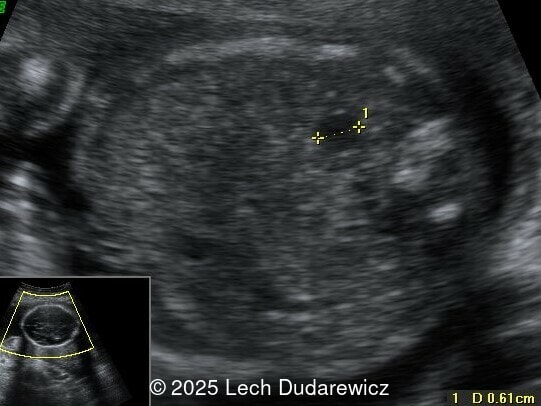

Structural anomalies were observed in multiple organ systems. The fetal skeleton showed hypoplastic iliac bones, rib deformities, hypoplastic scapulae, and excessive cervical spine lordosis. The fetal hands exhibited abnormal alignment of the fingers with restricted movement, and both feet were clubbed. Subcutaneous edema was noted over the forehead and occiput with a small cystic hygroma, along with increased nuchal fold thickness at 5.6mm, indicative of soft tissue edema.  Additional abnormalities included mild pyelectasis. The fetal stomach appeared nearly empty, likely reflecting impaired swallowing or associated anomalies. Polyhydramnios was also noted. External male genitalia appeared normal. Cardiac evaluation revealed multiple echogenic foci within the left ventricle and an atrioventricular septal defect. While the heart's overall structure and function were otherwise normal, these findings added to the overall suspicion of a syndromic condition.

Other findings on prenatal ultrasound include soft tissue edema, facial anomalies, cardiac defects, and renal abnormalities. Soft tissue findings, including increased nuchal fold thickness and generalized subcutaneous edema, are common in campomelic dysplasia. Macroglossia and facial dysmorphisms, such as a flat nasal bridge or hypertelorism, may be observed but can be subtle on prenatal imaging. Polyhydramnios, frequently noted in affected pregnancies, may result from impaired fetal swallowing due to craniofacial or neurologic abnormalities. Cardiac anomalies, while not pathognomonic, include ventricular septal defects and echogenic intracardiac foci. Renal abnormalities, such as pyelectasis or enlarged kidneys, may also be present. These findings, although non-specific, contribute to the syndromic picture of campomelic dysplasia.